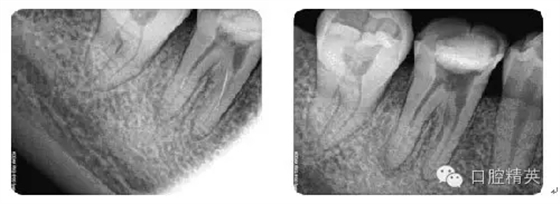

病例4:根管再治療

病例5:遺漏根管再治療